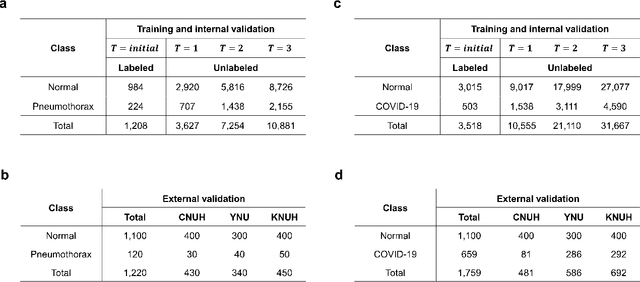

Abstract:Although deep learning-based computer-aided diagnosis systems have recently achieved expert-level performance, developing a robust deep learning model requires large, high-quality data with manual annotation, which is expensive to obtain. This situation poses the problem that the chest x-rays collected annually in hospitals cannot be used due to the lack of manual labeling by experts, especially in deprived areas. To address this, here we present a novel deep learning framework that uses knowledge distillation through self-supervised learning and self-training, which shows that the performance of the original model trained with a small number of labels can be gradually improved with more unlabeled data. Experimental results show that the proposed framework maintains impressive robustness against a real-world environment and has general applicability to several diagnostic tasks such as tuberculosis, pneumothorax, and COVID-19. Notably, we demonstrated that our model performs even better than those trained with the same amount of labeled data. The proposed framework has a great potential for medical imaging, where plenty of data is accumulated every year, but ground truth annotations are expensive to obtain.